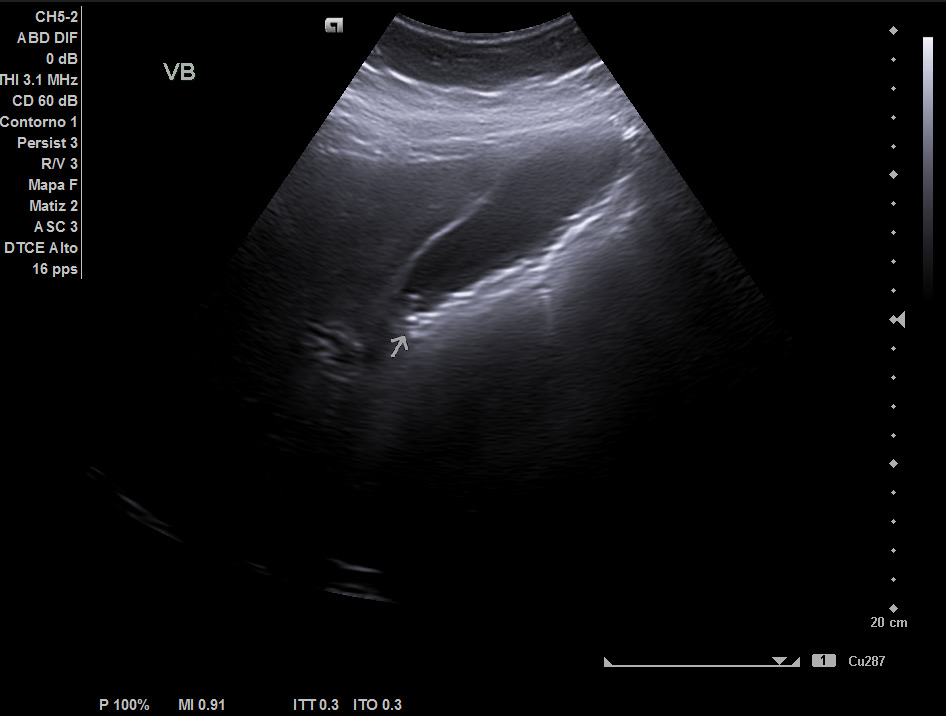

Hígado de tamaño, forma y ecoestructura conservadas, con parénquima homogéneo. Vena porta de calibre conservado. Colédoco dilatado, de 8,8 mm. Vesícula biliar de paredes gruesas y edematizadas (5,4 mm) en cara posterior, con contenido ecogénico y 2 microlitiasis en su infundíbulo.